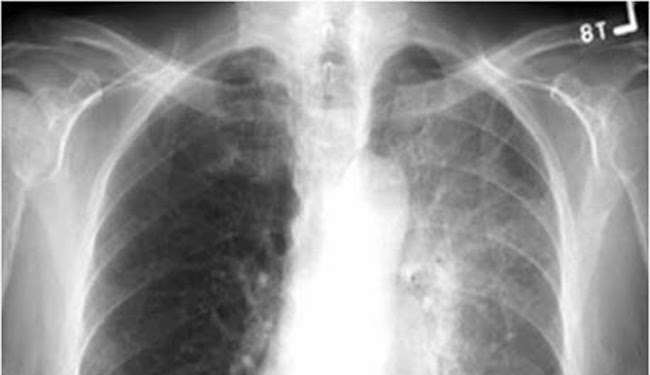

相較非小細胞肺癌,小細胞肺癌生長速度快,惡性程度也高。如果腫瘤僅在單側肺部或合併腫瘤附近淋巴轉移,可被放射治療範圍所涵蓋,此稱為「侷限期」;如果癌細胞已轉移到腦、骨頭、肝、心包膜、肋膜、腎上腺,則稱為「擴散期」。